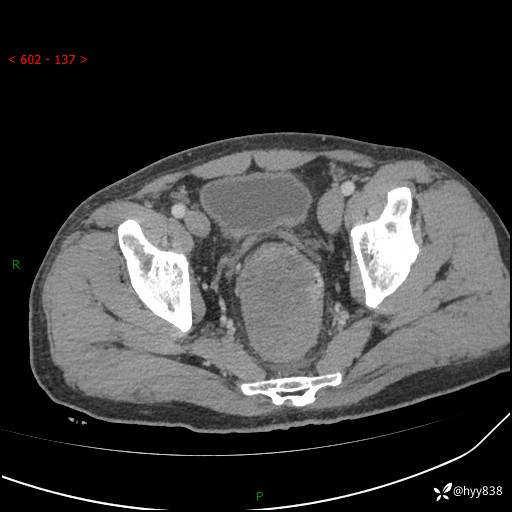

盆腔CT平扫+增强